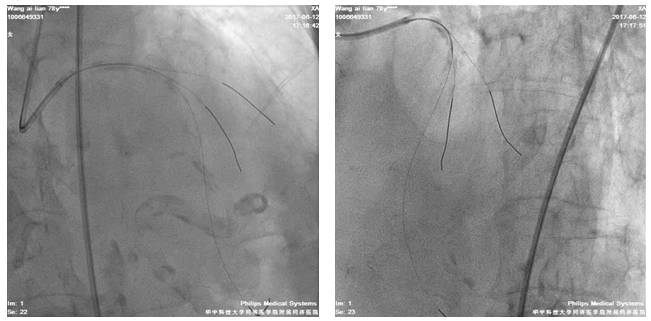

四日后,尝试左冠PCI术

股动脉路径

7F EBU3.5/GC

Runthrough NS,ASAHI SION,BMW导丝

2.5*20mm球囊扩张LAD10*12atm

先后与LAD远段-近段置入2.5*33mm、2.75*33mm、3.0*29mm DES支架,三支架串联